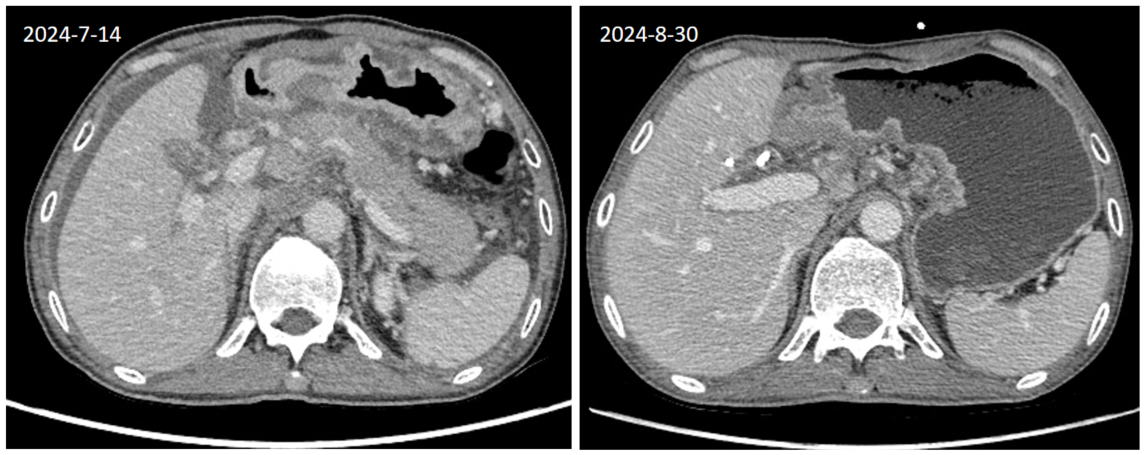

2025-8-30复查CT提示胃内病灶较前(2024-7-14CT对比)缩小,疗效评价为疾病稳定(SD)(缩小12%)(图1)。